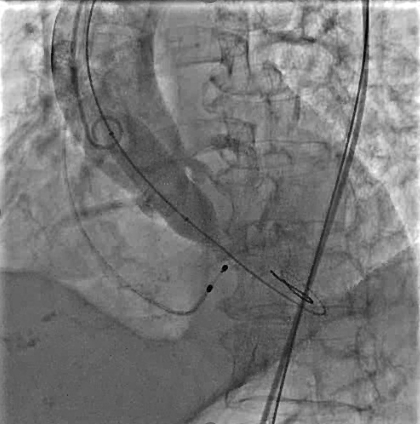

使用直头超滑导丝跨瓣后交换加硬导丝,行球囊扩张主动脉瓣,球囊扩张时行升主动脉造影,评估冠脉风险。

瓣膜定位及释放:将VenusA-Pro 23mm型号瓣膜系统送至主动脉瓣口处,以定位模式行造影,定位满意后释放瓣膜至工作位后,行定位造影,观察瓣膜位置及冠脉血流情况。瓣膜位置满意后完全释放瓣膜。